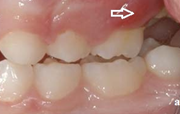

Esimese jäävmolaari ektoopiline lõikumine